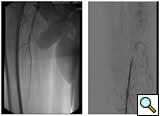

![]() |

Figure 1A: Angiogram |

Figure 1B: Following a day |

| Figure 1C: Angiogram shows restoration of limb perfusion. |

Case 1: An 84-year-old male with rest pain, who had undergone prior revascularization with covered stents, represents with recurrent rest pain. The prior stents had come close to the origin of the SFA and at that time there had been some narrowing. Exposure was provided by performing a cut down and patching the CFA-proximal SFA to the level of the stents, following which gentle thrombectomy was performed, and a wire passed down. The angiogram demonstrated a distal lesion at the adductor canal which contributed to the thrombosis (Figure 1A). The patient underwent a day of lysis, following which cryoablation was used to treat the distal lesion (Figure 1B) and completion angiogram showed restoration of limb perfusion (Figure 1C).